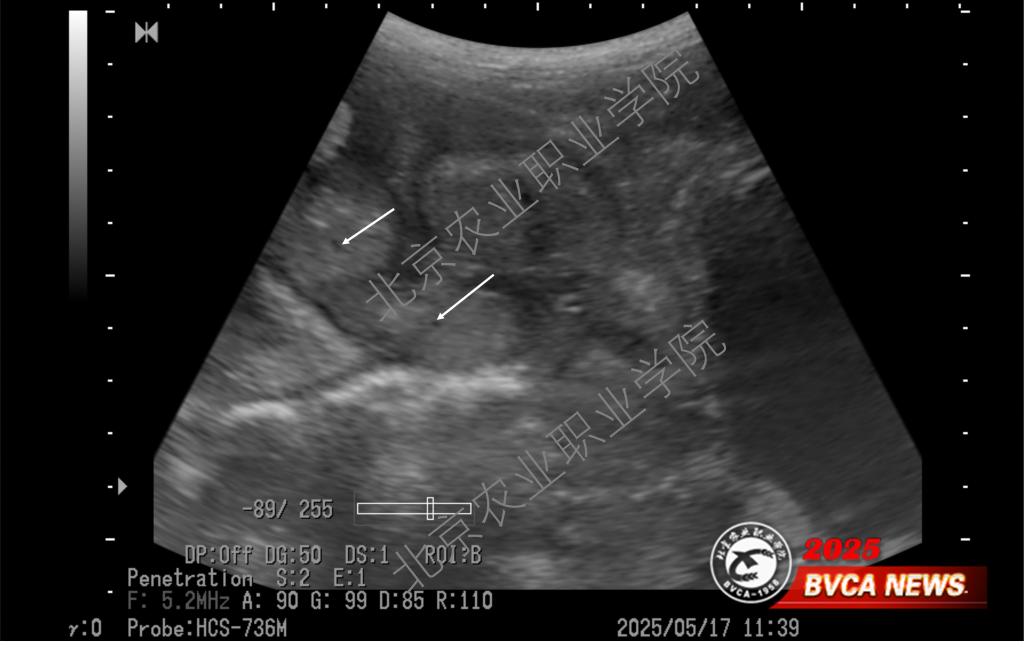

近日,受北京伟杰信生物科技有限公司邀请,动物科技学院兽医超声技术团队为该公司“母猪妊娠21天超声检查技术操作规范”项目提供了重要的技术支撑,并取得重大进展。团队首席专家姜晨副教授梳理了母猪不同体位超声扫查的方法,以便技术人员在不改变母猪体位的情况下做出准确诊断,最大程度上降低怀孕母猪不必要的应激。

近年来,best365姜晨副教授领衔的兽医超声技术团队积极推广超声影像技术在多种动物临床中的应用,并取得一系列技术成果。团队持续探索母猪孕早期超声检查的边界,目前最早可在排卵后第9天确认是否怀孕(可见直径约1mm的卵囊液)。此超声检查技术已达到国际前沿水平,为打开母猪孕初相关的科学研究之门提供了一把金钥匙。